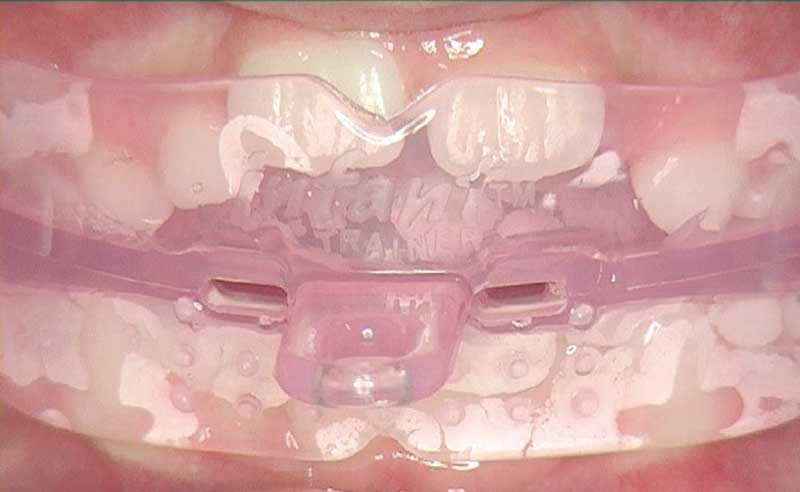

Dans notre clinique habituelle, nous devons intégrer les traitements de prévention et d’interception. Travailler sur les dysfonctions de la zone oro-faciale permettra d’éviter l’aggravation des malformations et favorisera une croissance harmonieuse de la face. La notion de temps est importante, c’est pourquoi il est nécessaire d’intervenir le plus tôt possible. Des appareils fonctionnels, souples et standards, avec ou sans indentation, vont permettre un déverrouillage des arcades dentaires et servir de guide d’éruption. Ces traitements sont très chronophages et vont nécessiter une modification de notre mode de fonctionnement au sein du cabinet.

L’interception des malocclusions à l’aide d’éducateurs fonctionnels fait partie de notre arsenal thérapeutique. Elle prend en compte l’ensemble des fonctions oro-faciales perturbées et permet de changer le comportement neuromusculaire du patient pour neutraliser au mieux ses dysfonctions. Cette approche permet de changer la fonction et successivement la forme en agissant dans les trois dimensions de l’espace sous condition d’avoir encore un potentiel de croissance suffisant (1).